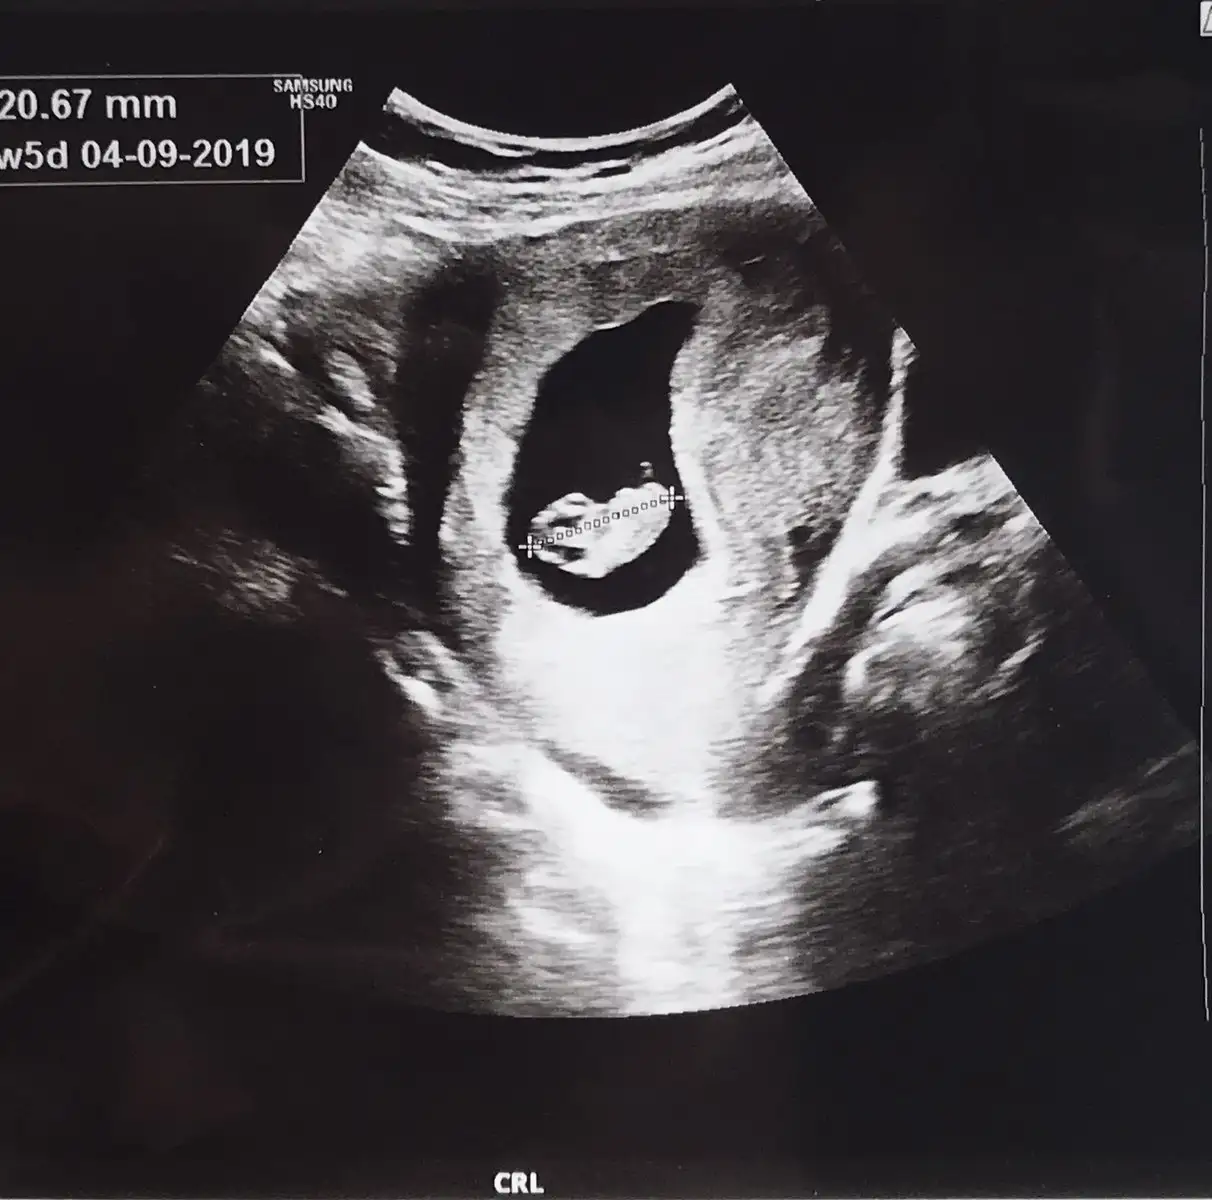

8 haftalık görüntü tahmin alabilirmiyim

Eklentiler

• 5DF6B3C7-374F-4E15-913C-1AB0BFEC0082.webp

5DF6B3C7-374F-4E15-913C-1AB0BFEC0082.webp

12,9 KB · Görüntüleme: 95